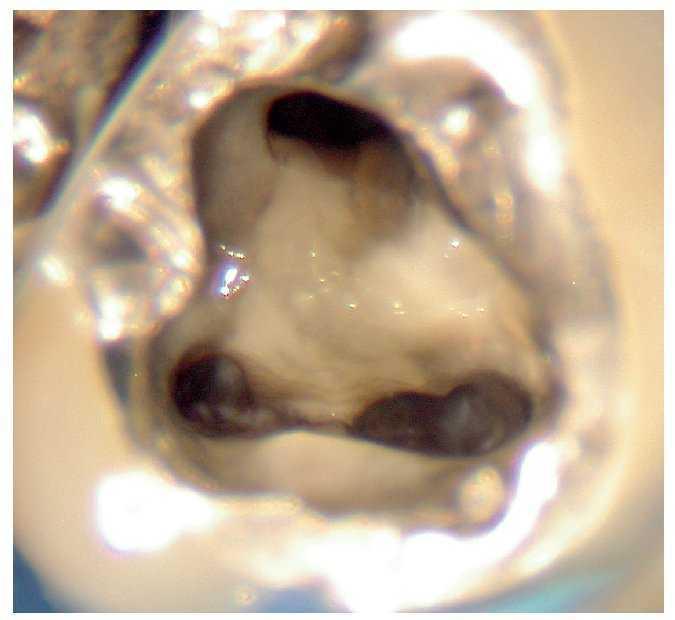

Figura 2c. Situación después de la apertura cameral: la obturación existente carece de sellado marginal. No se identificó la luz del conducto radicular original. Alrededor del material de obturación se detecta tejido necrótico de aspecto negruzco, sobre todo en la zona distal donde el conducto radicular adopta una forma marcadamente ovalada. Se pasó por alto y no se preparó el istmo frecuentemente existente en los molares inferiores entre el conducto mesiovestibular y el conducto mesiolingual.

Figura 2d. Después de limpiar el suelo de la cámara pulpar salen a la luz las estructuras del sistema de conductos radiculares que se pasaron por alto en el primer tratamiento.